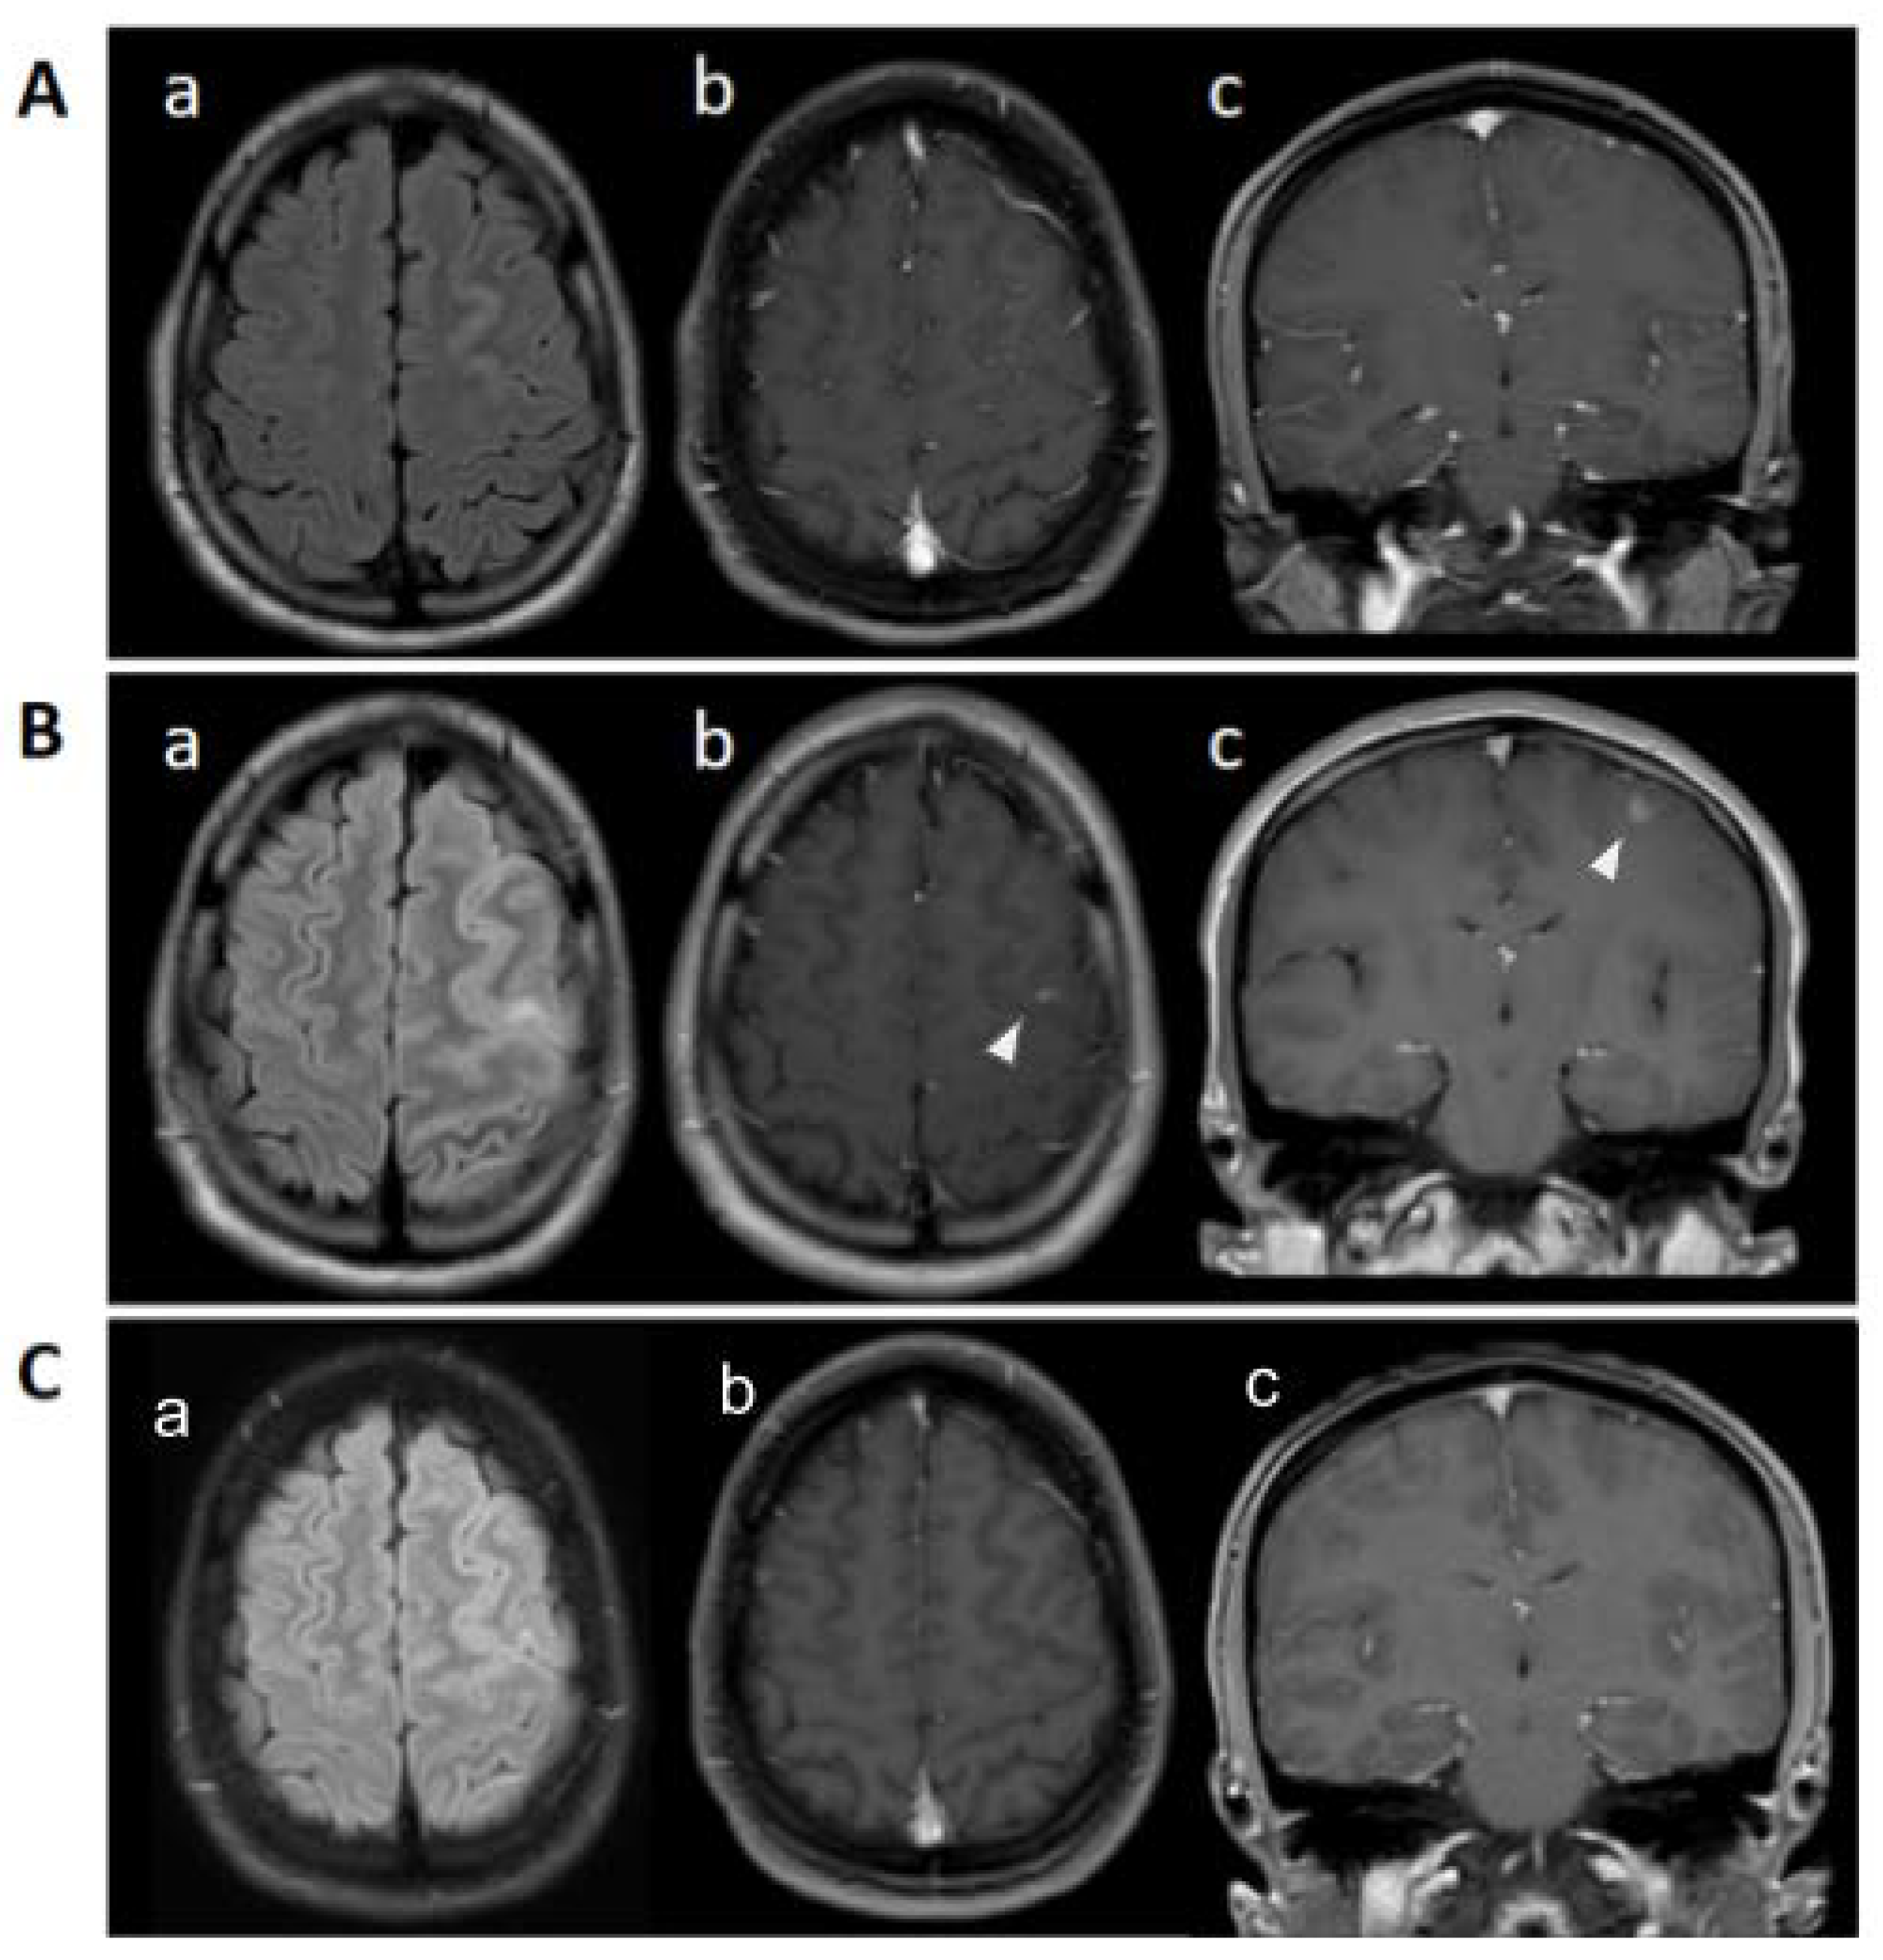

Post-Infectious Focal Encephalitis Due to COVID-19

Case report